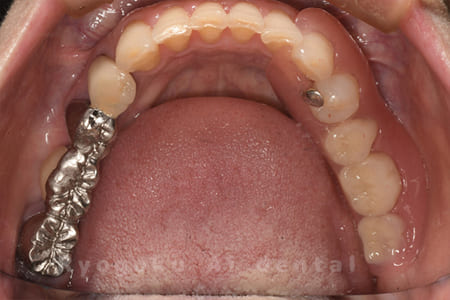

- 原因

- 右下5・6番歯根破折

- 治療内容

- ノンクラスプデンチャー

右下の歯が割れているとのことでご来院された患者様です。全身疾患も考慮し、目立たない入れ歯を相談して決定し、大変満足いただけました。